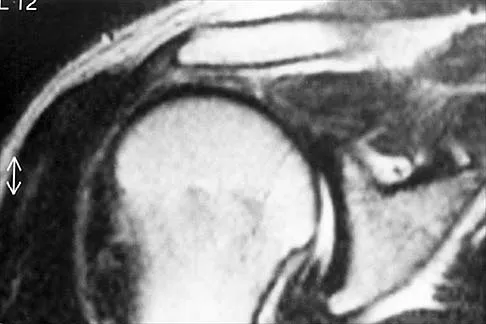

Figure 42 is a transverse MRI scan of the left shoulder. The arrow points to which of the following structures?